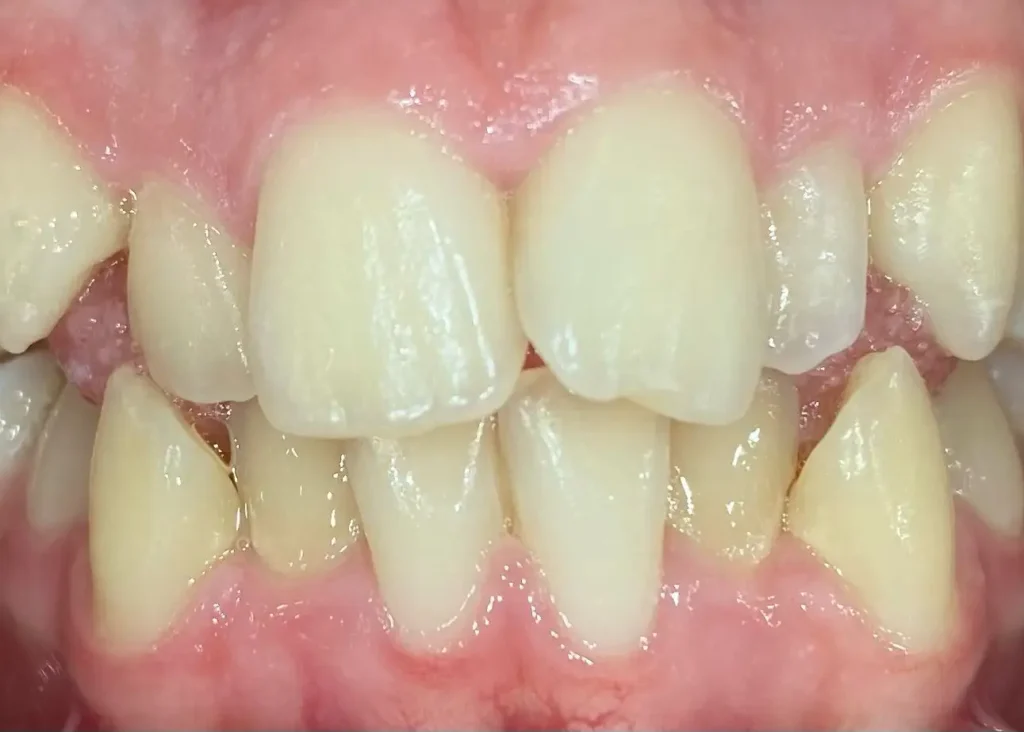

Casos clínicos de ortodoncia en CDPA